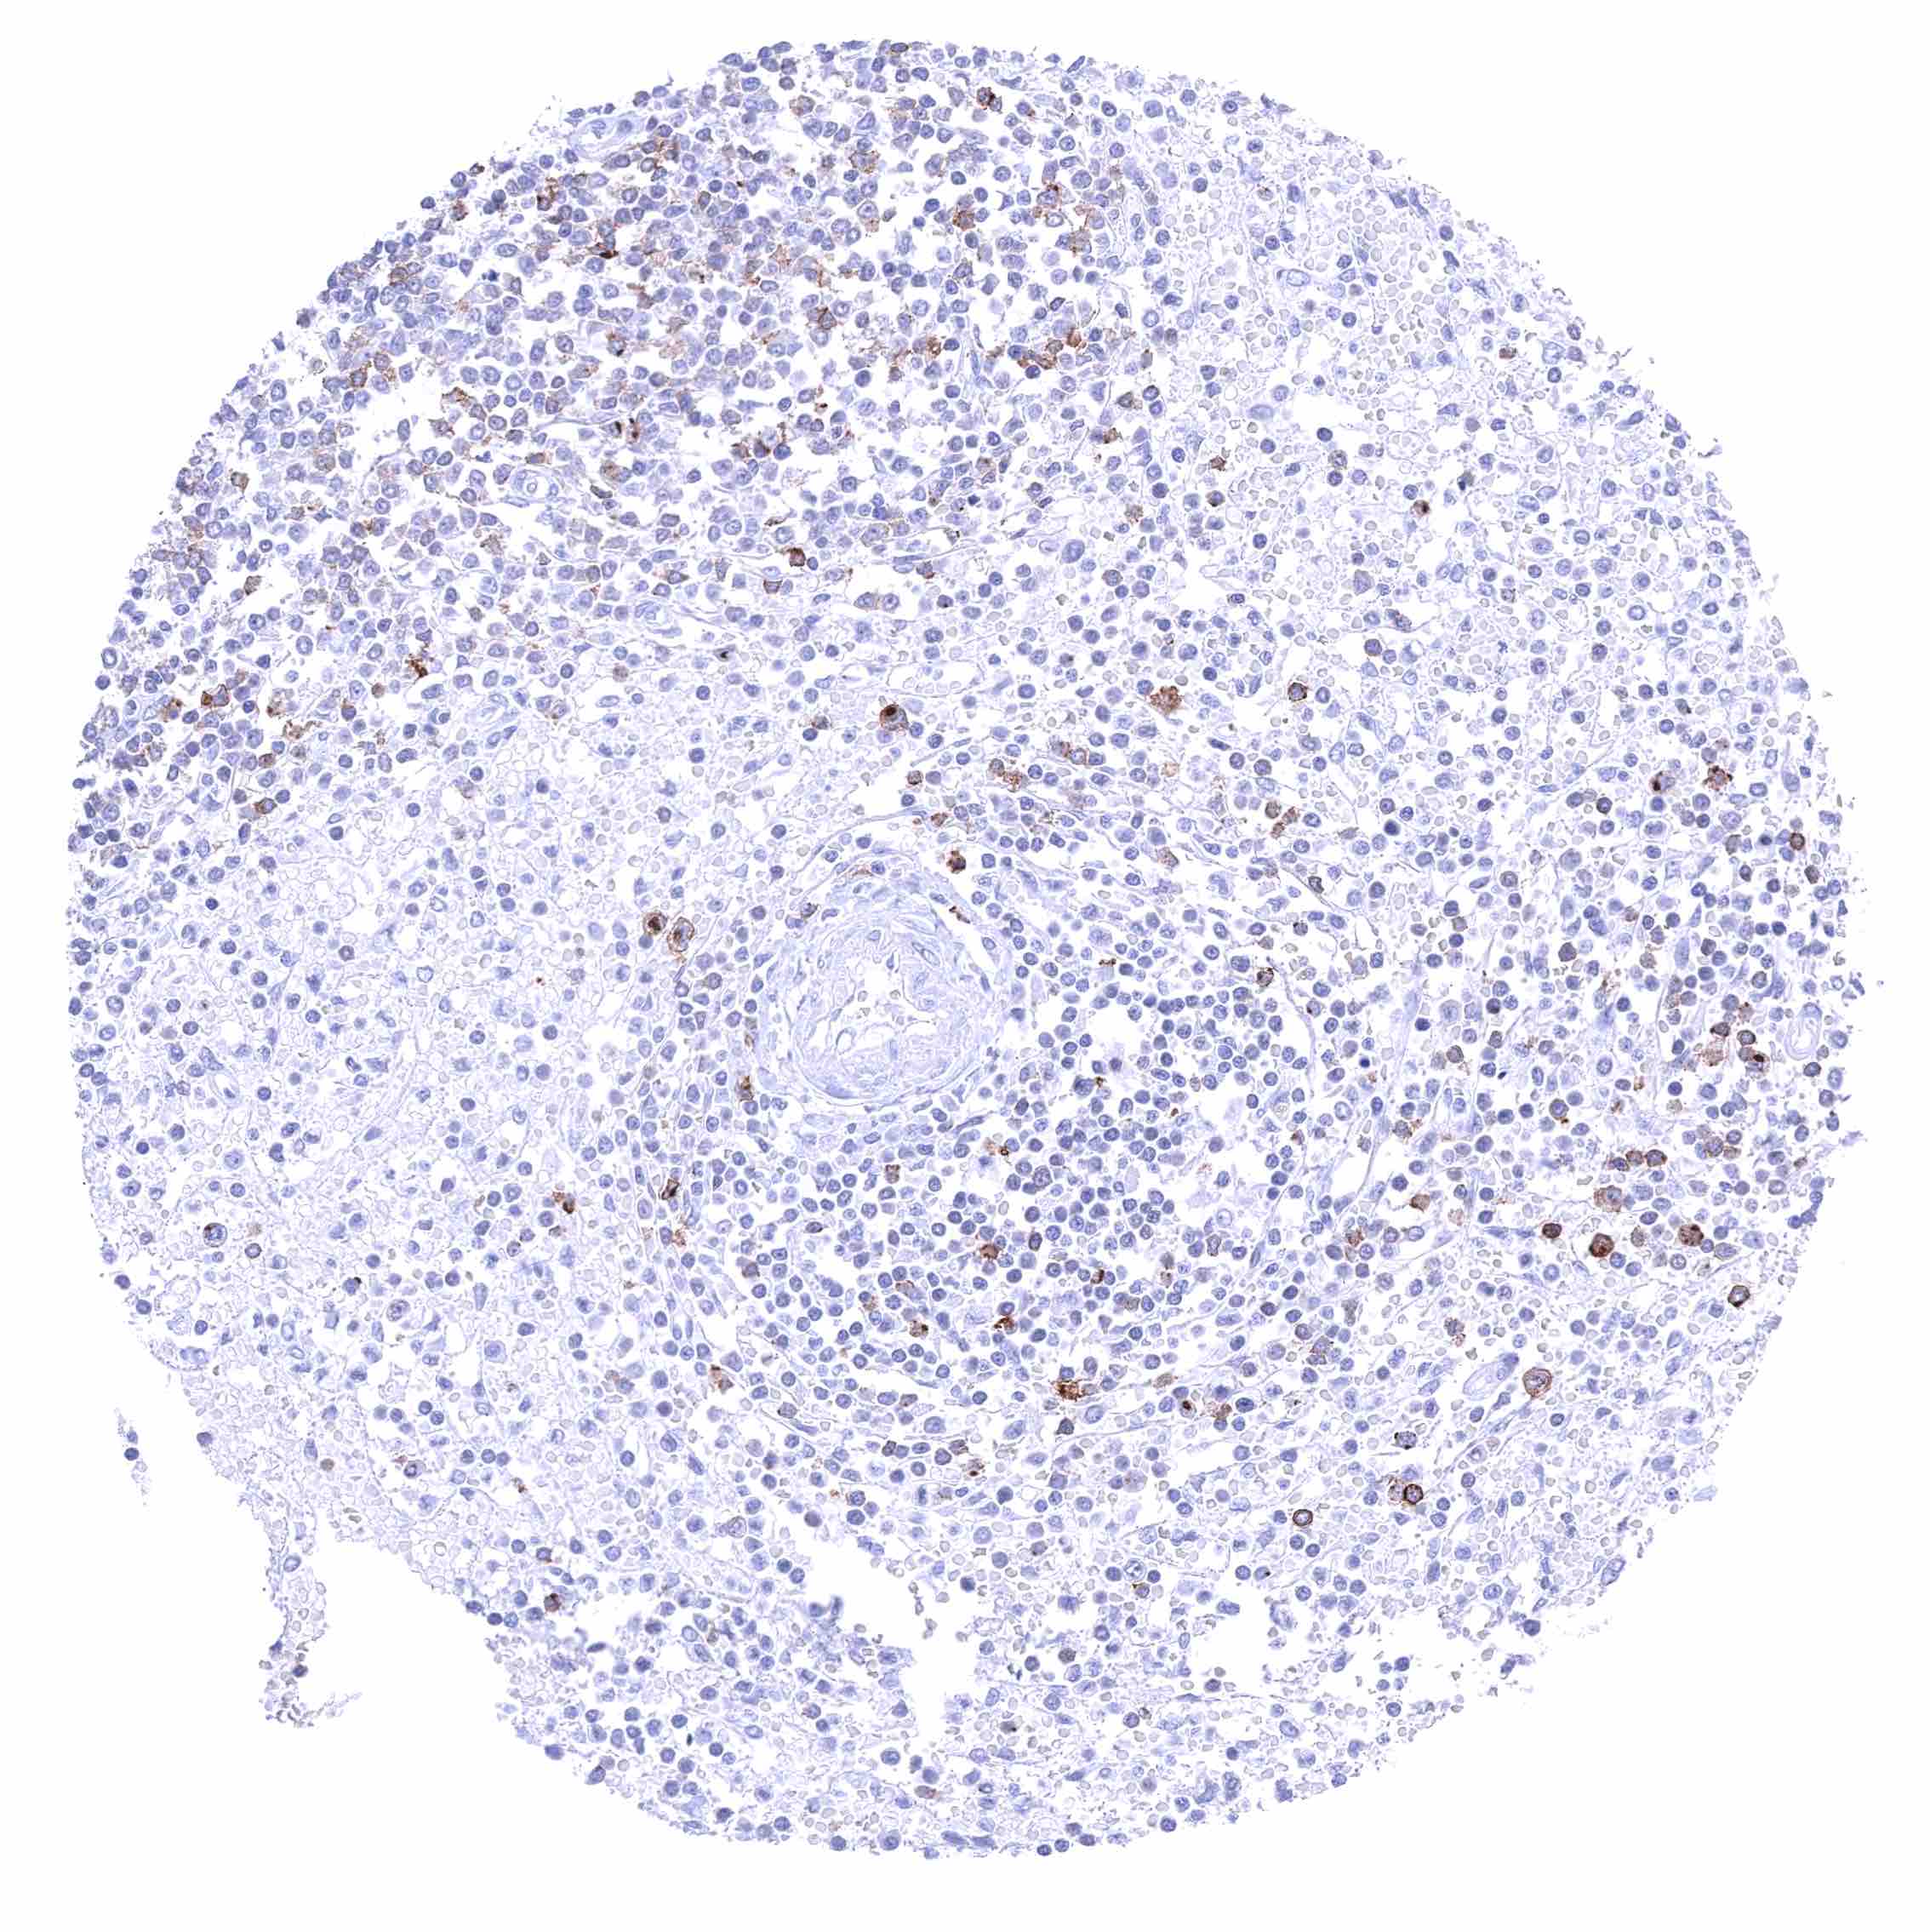

| Lymph node | Membranous CD70 staining of variable intensity in subsets of inflammatory cells (mostly lymphocytes). Most CD70 positive cells are interfollicular. | |

| Spleen | Membranous CD70 staining of variable intensity in a fraction of cells. | |

| Thymus | Membranous CD70 staining of variable intensity in a small subset of cells. | |

| Tonsil | Membranous CD70 staining of variable intensity in subsets of inflammatory cells (mostly lymphocytes). Most CD70 positive cells are interfollicular. Squamous epithelium remains CD70 negative. | |